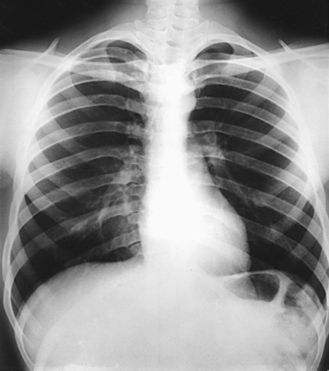

In radiography of the ribs, an IR 14 × 17 inches (35 × 43 cm) should be used to identify the ribs involved and to determine the extent of trauma or pathologic condition. An IR 11 × 14 inches (28 × 36 cm) is often used with smaller patients. Projections can be made in recumbent and upright positions. If the area in question involves the first and last ribs, additional images may be required to show the affected area better (Fig. 9-30).

After the lesion is localized, the next step is to determine (1) the position required to place the affected rib region parallel with the plane of the IR and (2) whether the radiograph should be made to include the ribs above or below the diaphragm.

The anterior portion of the ribs, usually referred to simply as the anterior ribs, is often examined with the patient facing the IR for a PA projection (Fig. 9-31). The posterior portion of the ribs, or the posterior ribs, is more commonly radiographed with the patient facing the x-ray tube in the same manner as for an AP projection (Fig. 9-32).

The axillary portion of the ribs is best shown using an oblique projection. Because the lateral projection results in superimposition of the two sides, it is generally used only when fluid or air levels are evaluated after rib fractures.